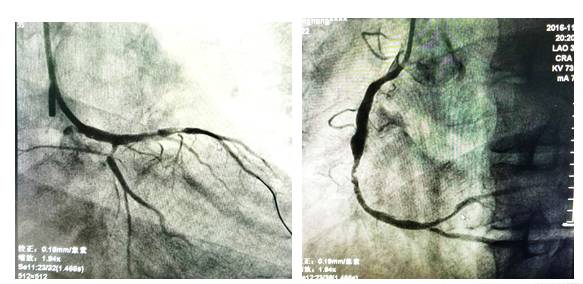

19:37造影:严重的左主干病变!

19:53 开始PCI

20:06 球扩后植入1枚支架

20:16 最后结果

◆ECMO 保护下行CAG+PCI干预RCA;